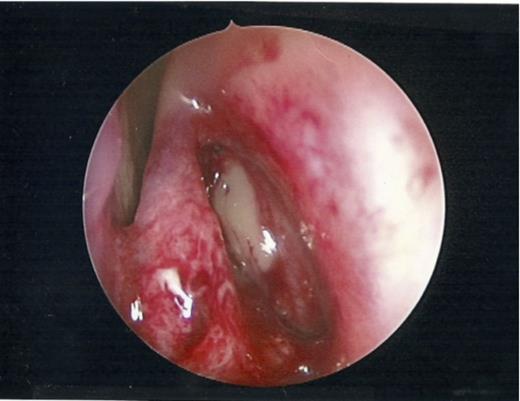

For our case, the patient was placed under general anaesthetic. Under endoscopic visualisation, a guidewire was passed within a catheter into the frontal sinus. The moment the guidewire passed into the recess there was a gush of mucopus and the forehead swelling gradually resolved. The position of this instrument was confirmed with trans-illumination – which was externally visible. Once in the correct position, a balloon was advanced over the guidewire and its position within the ostia verified using endoscopic visualisation. The balloon was subsequently inflated to 12 atmospheres pressure. Following this step, a large volume of mucopus was visualised draining from the ostium. An irrigation catheter was finally used to flush the sinus of any remaining mucopus and debris. Post- procedure, good ventilation of the ostia was visualised (Figure 2).

Patent ostia visualised endoscopically post dilatation with free drainage of mucopus.